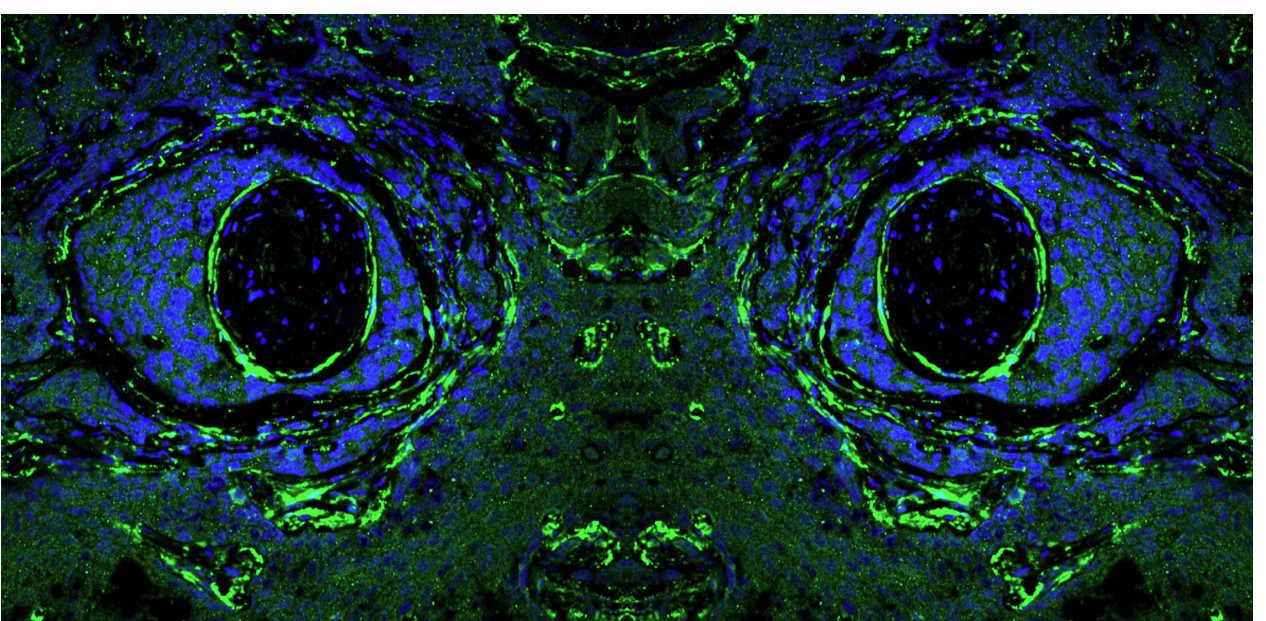

Research at the Pfizer-University of Granada-Junta de Andalucía Centre for Genomics and Oncology Research (GENYO) is organised into two main areas: Functional Genomics, which corresponds to the basic area, and Personalised Medicine, focused on clinical applications. These areas are structured into strategic lines. The Functional Genomics area focuses on the study of the human genome and cancer genomics, addressing the fundamental mechanisms of genetic and molecular biology. The area of Personalised Medicine focuses on the detection, diagnosis, monitoring and prognosis of diseases, as well as the design and implementation of advanced therapies, with the aim of translating scientific knowledge into personalised solutions for patients. This structure allows GENyO to integrate basic and applied research, driving significant advances in the field of genomics and oncology.